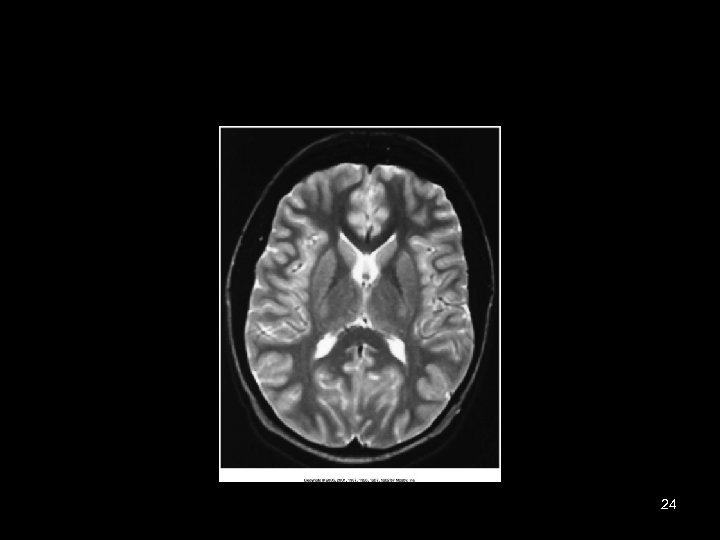

24

Diagnostic Applications • Most common anatomy examined is – Head, chest and abdomen • Exam of choice for: – Head trauma – CVA • Also useful for: – – – – – Infarctions Hemorrhage Disk herniations Craniofacial fractures and tumors Cancers Hydrocephalus Degenerative diseases Inflammatory infections Congenital disorders 52